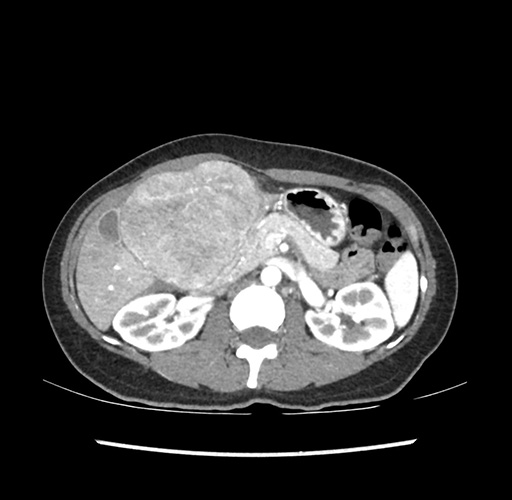

Imaging Analysis

Look through the patient's CT scan to identify any areas of concern for the necessary procedure.

Based on your CT findings, which issue(s) would give reason for "planned slowing down moment(s)" in this case?